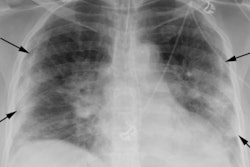

Investigators from Brescia, Italy, have revealed details of their chest x-ray scoring system for evaluating and tracking COVID-19 findings. They unveiled their results on 1 May in La Radiologia Medica.

But there must be a sound scoring framework. The current chest x-ray scoring system is a five-point tool designed for nonradiologists to assess hospitalized patients with acute respiratory infection. As an alternative, Borghesi and Maroldi developed a scoring system to help radiologists quantify and monitor COVID-19 pneumonia in hospitalized patients.

The scoring system included two steps. First, the lungs were divided into six zones on frontal chest projection (two upper zones, two middle, and two lower). Second, each zone was scored based on the following:

- 0: No lung abnormalities

- 1: Interstitial infiltrates

- 2: Interstitial and alveolar infiltrates (interstitial predominance)

- 3: Interstitial and alveolar infiltrates (alveolar predominance)

The researchers added the scores of the six lung zones for an overall score between 0 and 18. A thoracic radiologist independently assessed each of the 100 reports, evaluating the original score. Borghesi and Maroldi then compared the agreement between the initial scoring and the assessment scoring using kappa values.

The median chest x-ray score for the original exams using the system was 6.5, while the median score assigned by the second reader was 7. Kappa agreement between the two scores was 0.82. The team also found that both the initial and second-reader scores were higher for patients who died than for those who were discharged (p ≤ 0.002).